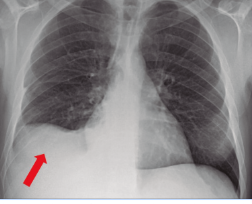

Señora Tijuana, trabaja en una granja de leche bronca. Presenta tos titica. Tuberculina > 5, siguiente cuadro RX.

¿que tinción usara patología para confirmar el dx?

A

Nódulo de góhn

TINCIÓN - ZIEHL NIELSEN

TB

*langhans